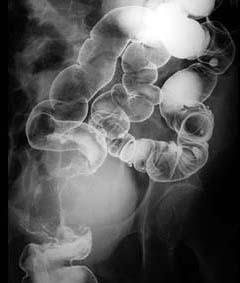

有关直肠癌下列哪些说法正确 ( )A、可伴有肠梗阻症状B、多诉有黏液血便C、好发于直肠壶腹D、组织学多为腺癌E、其转移部位越高越复杂

问题 有关直肠癌下列哪些说法正确 ( )

选项 A、可伴有肠梗阻症状 B、多诉有黏液血便 C、好发于直肠壶腹 D、组织学多为腺癌 E、其转移部位越高越复杂

答案 ABCD